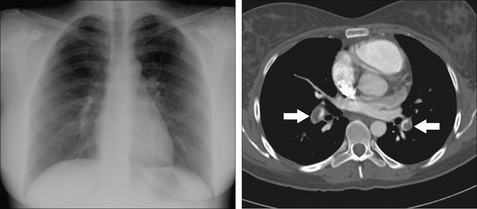

Figure 28.3 Chronic dyspnoea. Shadowing in the right lower zone. Apply Golden Rule 3—you only look for what you know. CXR conclusion—collapse of the right lower lobe.

Figure 28.13 Female. Age 24. Acute dyspnoea. Normal CXR. The CT pulmonary angiogram reveals large thrombi in the pulmonary arteries (arrows). Acute pulmonary embolism.